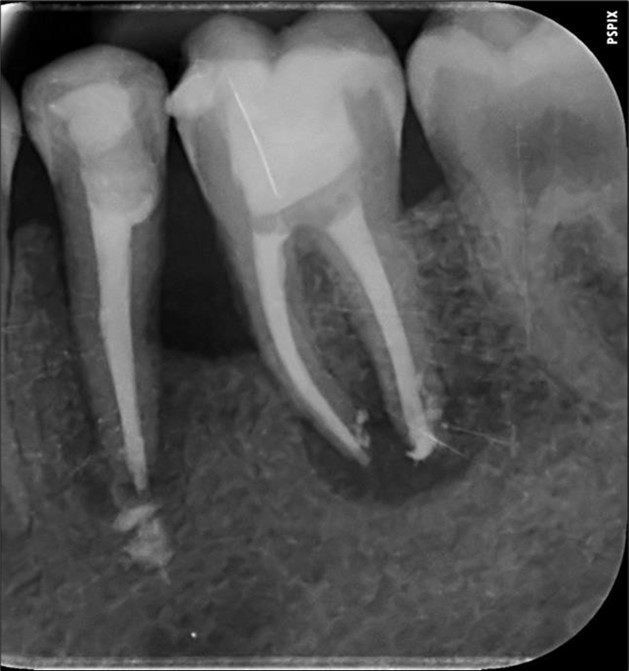

Complete healing of periapical lesions and treatment of teeth 26 and 16 with advanced endo-perio lesions posed challenges due to the patient’s delayed supplementation. In this case, surgical endodontic procedures and the extraction of teeth with advanced endo-perio lesions were considered risky because of the underlying metabolic healing impairment. Figure 3

Figure 3.6. 7, 8, 9, and 10 showing postoperative periapical radiographs of these endodontic treatments.